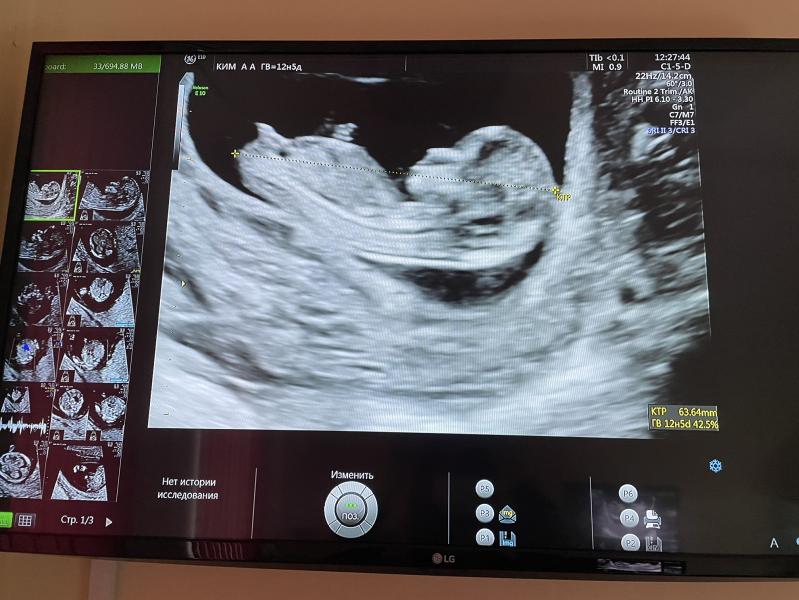

Сегодня ходила на первый скрининг😅 оооо, божеее

Эти чувства, смотришь на экран и не веришь, что этот человечек живет в тебе, не передаваемые ощущения🥰 предположили девчонку😻